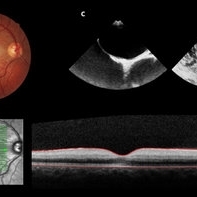

A 19-year-old man presented in emergency department (ED) reporting painless blurred vision in the right eye that started one hour ago while he was doing exercise. His medical history was unremarkable. On examination, best corrected visual acuity in the right eye was counting fingers (20cm), right relative afferent pupillary defect was evident, intraocular pressure and anterior segment were normal. Dilated retinal examination revealed retinal whitening in the macular area and a cherry red spot (panel A) that became increasingly evident with time. Patient denied other systemic symptoms. Macular spectral domain optic coherence tomography showed hyperreflectivity of the inner retina (panel B). In ED, patient underwent ocular massage using a three-mirror contact lens and topical hypotensive treatment. Additionally, oral antiplatelet and hyperbaric oxygen treatment were initiated. Further investigation was performed and fluorescein angiography revealed a delay in arterial filling. Blood tests including hypercoagulation disorders investigation, plain chest radiography and electrocardiogram were unremarkable. Patent foramen ovale was diagnosed in transesophageal echocardiogram (panel C), anticoagulation therapy was promptly initiated and percutaneous closure of patent foramen ovale was done successfully a few weeks later. Final best corrected visual acuity was 20/200 and macula developed atrophy.

Condition/keywords: central retinal artery occlusion (CRAO), patent foramen ovale